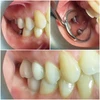

فقدان الأسنان

علاج الزرع